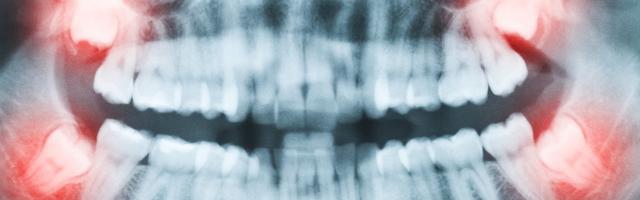

I pro e i contro della radiografia dentale sono sempre di piú al centro dell'acceso dibattito riguardante appunto i vantaggi e gli svantaggi di questo misterioso strumento diagnostico. Un mistero sembra avvolgere, infatti, le radiografie, le protagoniste principali nella cura e nella prevenzione dei problemi del cavo orale.